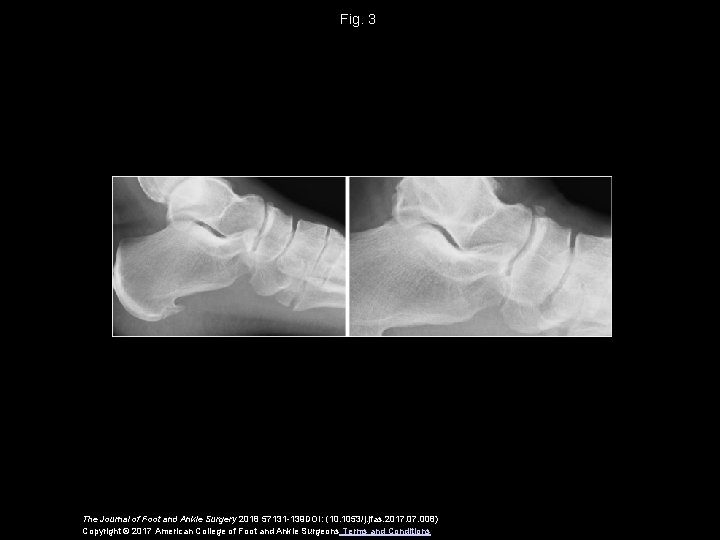

Fig. 3 The Journal of Foot and Ankle Surgery 2018 57131 -139 DOI: (10. 1053/j. jfas. 2017. 008) Copyright © 2017 American College of Foot and Ankle Surgeons Terms and Conditions